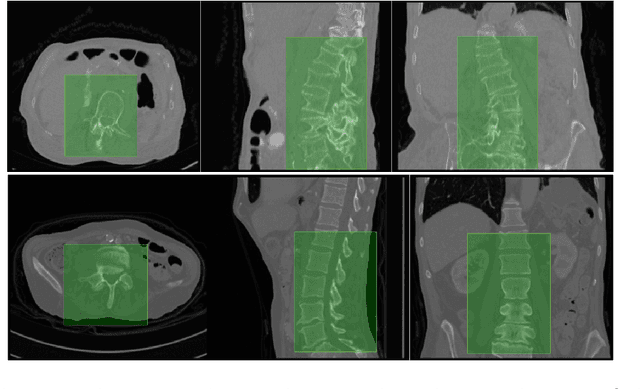

Multi-class segmentation of vertebrae is a non-trivial task mainly due to the high correlation in the appearance of adjacent vertebrae. Hence, such a task calls for the consideration of both global and local context. Based on this motivation, we propose a two-staged approach that, given a computed tomography dataset of the spine, segments the five lumbar vertebrae and simultaneously labels them. The first stage employs a multi-layered perceptron performing non-linear regression for locating the lumbar region using the global context. The second stage, comprised of a fully-convolutional deep network, exploits the local context in the localised lumbar region to segment and label the lumbar vertebrae in one go. Aided with practical data augmentation for training, our approach is highly generalisable, capable of successfully segmenting both healthy and abnormal vertebrae (fractured and scoliotic spines). We consistently achieve an average Dice coefficient of over 90 percent on a publicly available dataset of the xVertSeg segmentation challenge of MICCAI 2016. This is particularly noteworthy because the xVertSeg dataset is beset with severe deformities in the form of vertebral fractures and scoliosis.